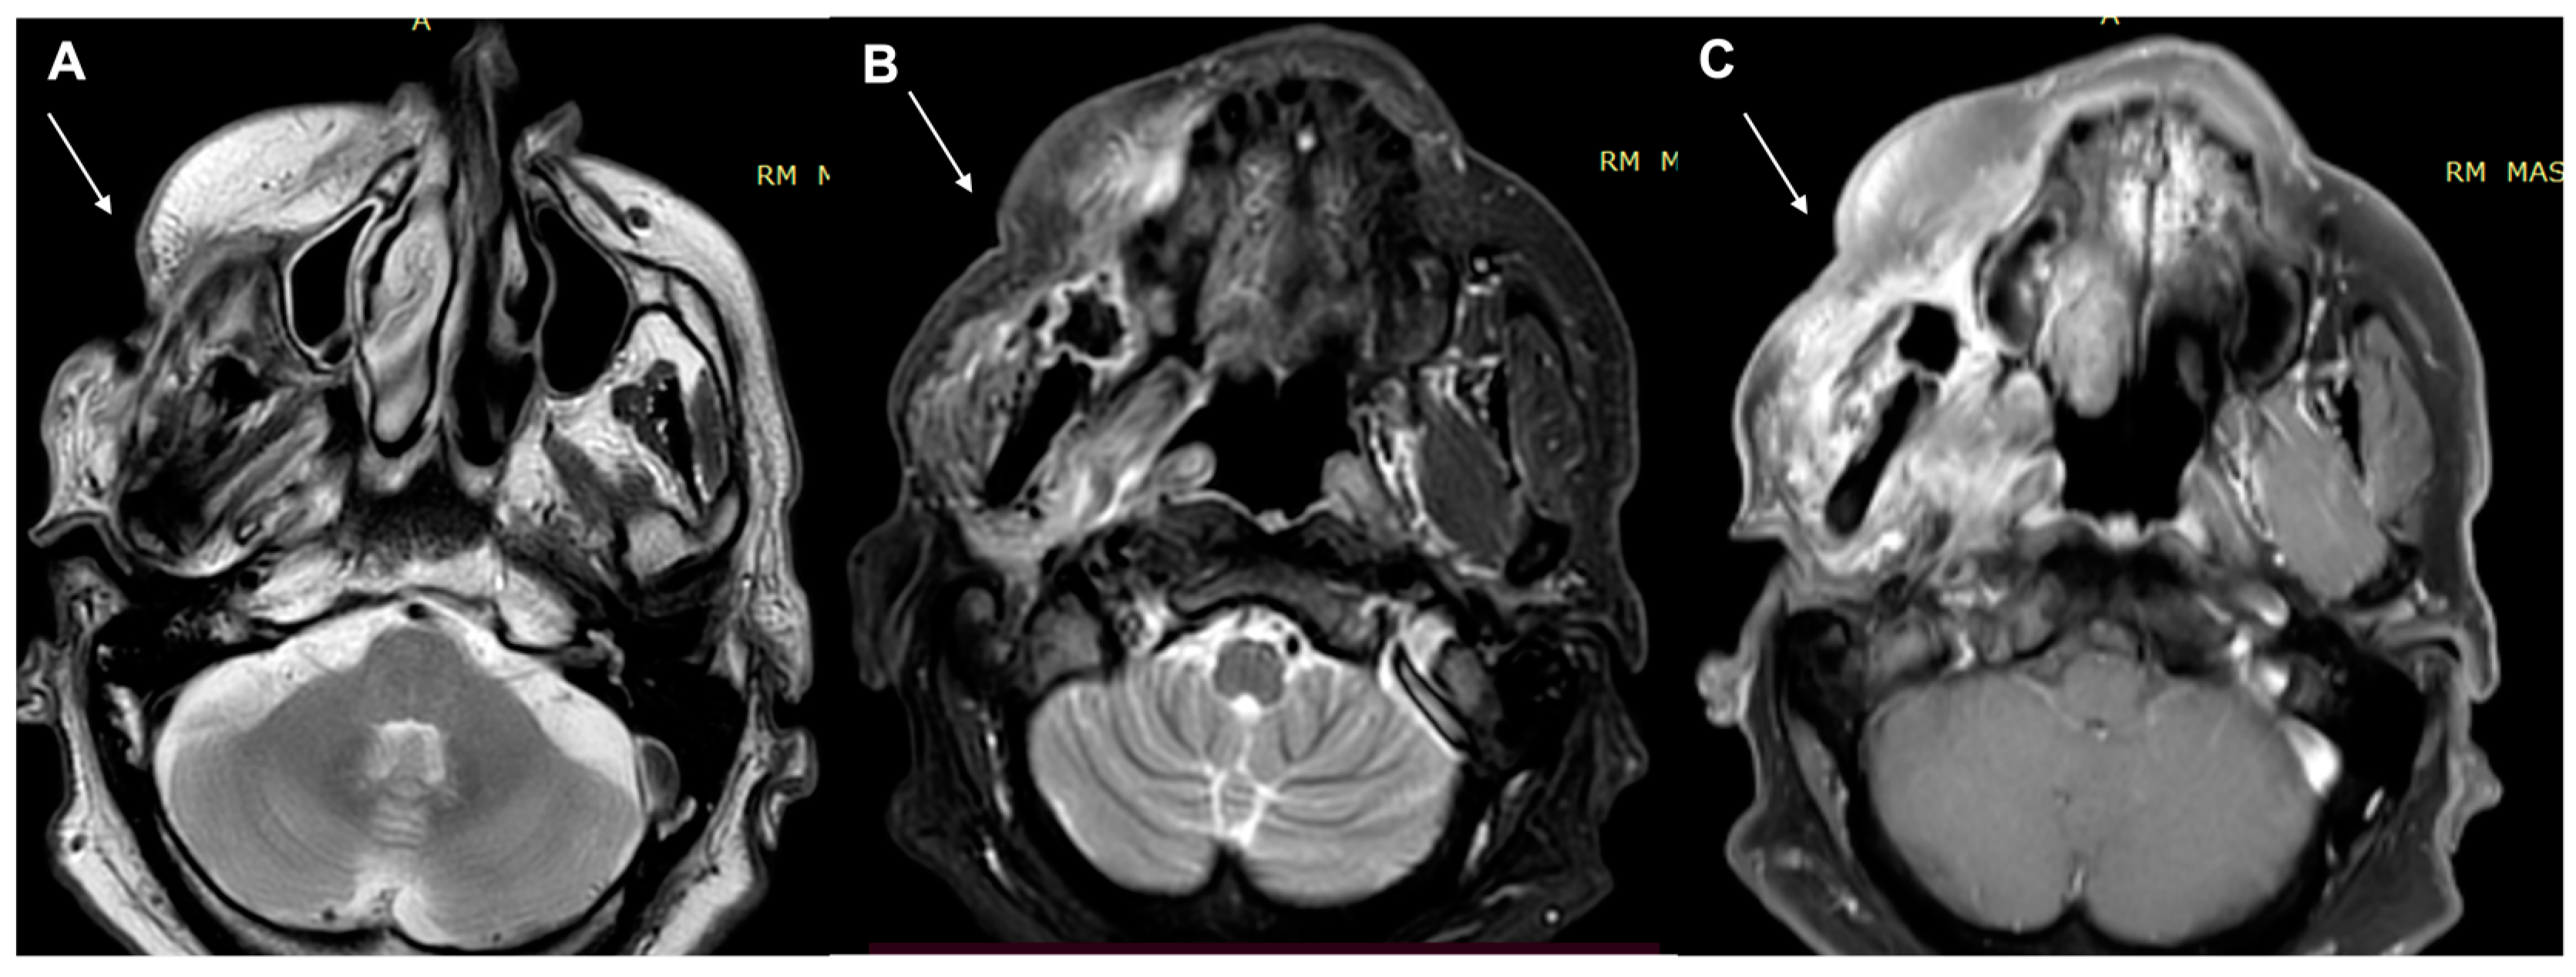

- Kawaguchi, M.; Kato, H.; Tomita, H.; Hara, A.; Suzui, N.; Miyazaki, T.; Matsuyama, K.; Seishima, M.; Matsuo, M. Magnetic Resonance Imaging Findings Differentiating Cutaneous Basal Cell Carcinoma from Squamous Cell Carcinoma in the Head and Neck Region. Korean J. Radiol. 2020, 21, 325–331. [Google Scholar] [CrossRef] [PubMed]

- Kawaguchi, M.; Kato, H.; Tomita, H.; Hara, A.; Suzui, N.; Miyazaki, T.; Matsuyama, K.; Seishima, M.; Matsuo, M. MR imaging findings for differentiating cutaneous malignant melanoma from squamous cell carcinoma. Eur. J. Radiol. 2020, 132, 109212. [Google Scholar] [CrossRef] [PubMed]

- Sheng, M.; Tang, M.; Lin, W.; Guo, L.; He, W.; Chen, W.; Li, K.; Liu, J.; Xiao, C.; Li, Y. The value of preoperative high-resolution MRI with microscopy coil for facial nonmelanoma skin cancers. Ski. Res. Technol. 2021, 27, 62–69. [Google Scholar] [CrossRef]